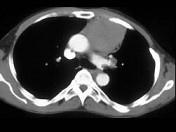

男,57岁,胸部隐痛2月余,请结合影像学检查,选出最可能的诊断 ( )A.纵隔畸胎瘤B.淋巴瘤C.支气管囊肿D.胸内甲状腺肿E.胸腺瘤

问题 男,57岁,胸部隐痛2月余,请结合影像学检查,选出最可能的诊断 ( )

选项 A.纵隔畸胎瘤 B.淋巴瘤 C.支气管囊肿 D.胸内甲状腺肿 E.胸腺瘤

答案 E